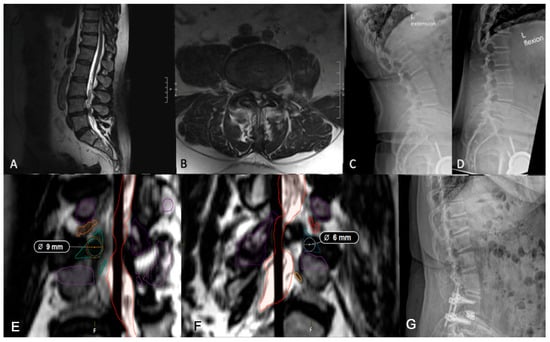

3.3. Measuring Kambin’s Triangle